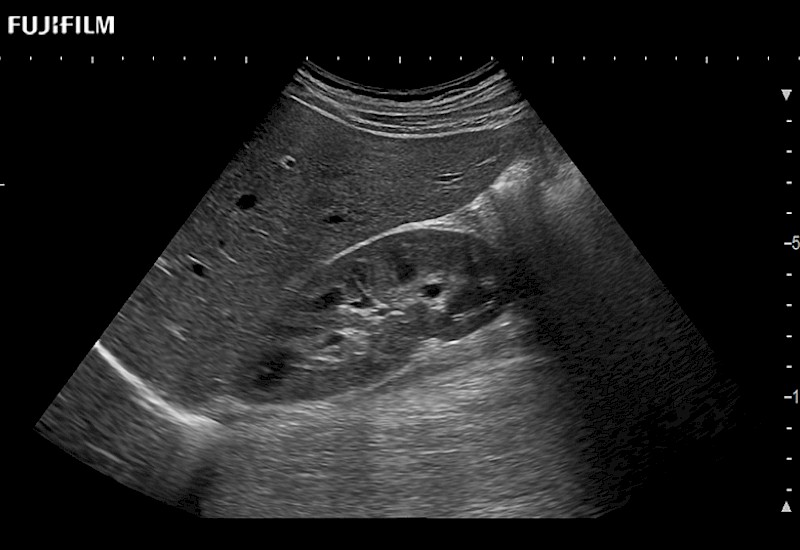

for use during general and laparoscopic procedures: Tumor localization & staging, Ablation, Resection, Biopsy, Transplant, Abdominal exploration, Robotic surgery

The ARIETTA 650 DI combines trusted Fujifilm Healthcare technologies and features tailored for surgical oncology.

Designed to meet the demands of surgeons, the ARIETTA 650 DI offers precise guidance. Its advanced capabilities and large, intuitive display offer accurate and efficient care in operating rooms and specialized surgical settings.